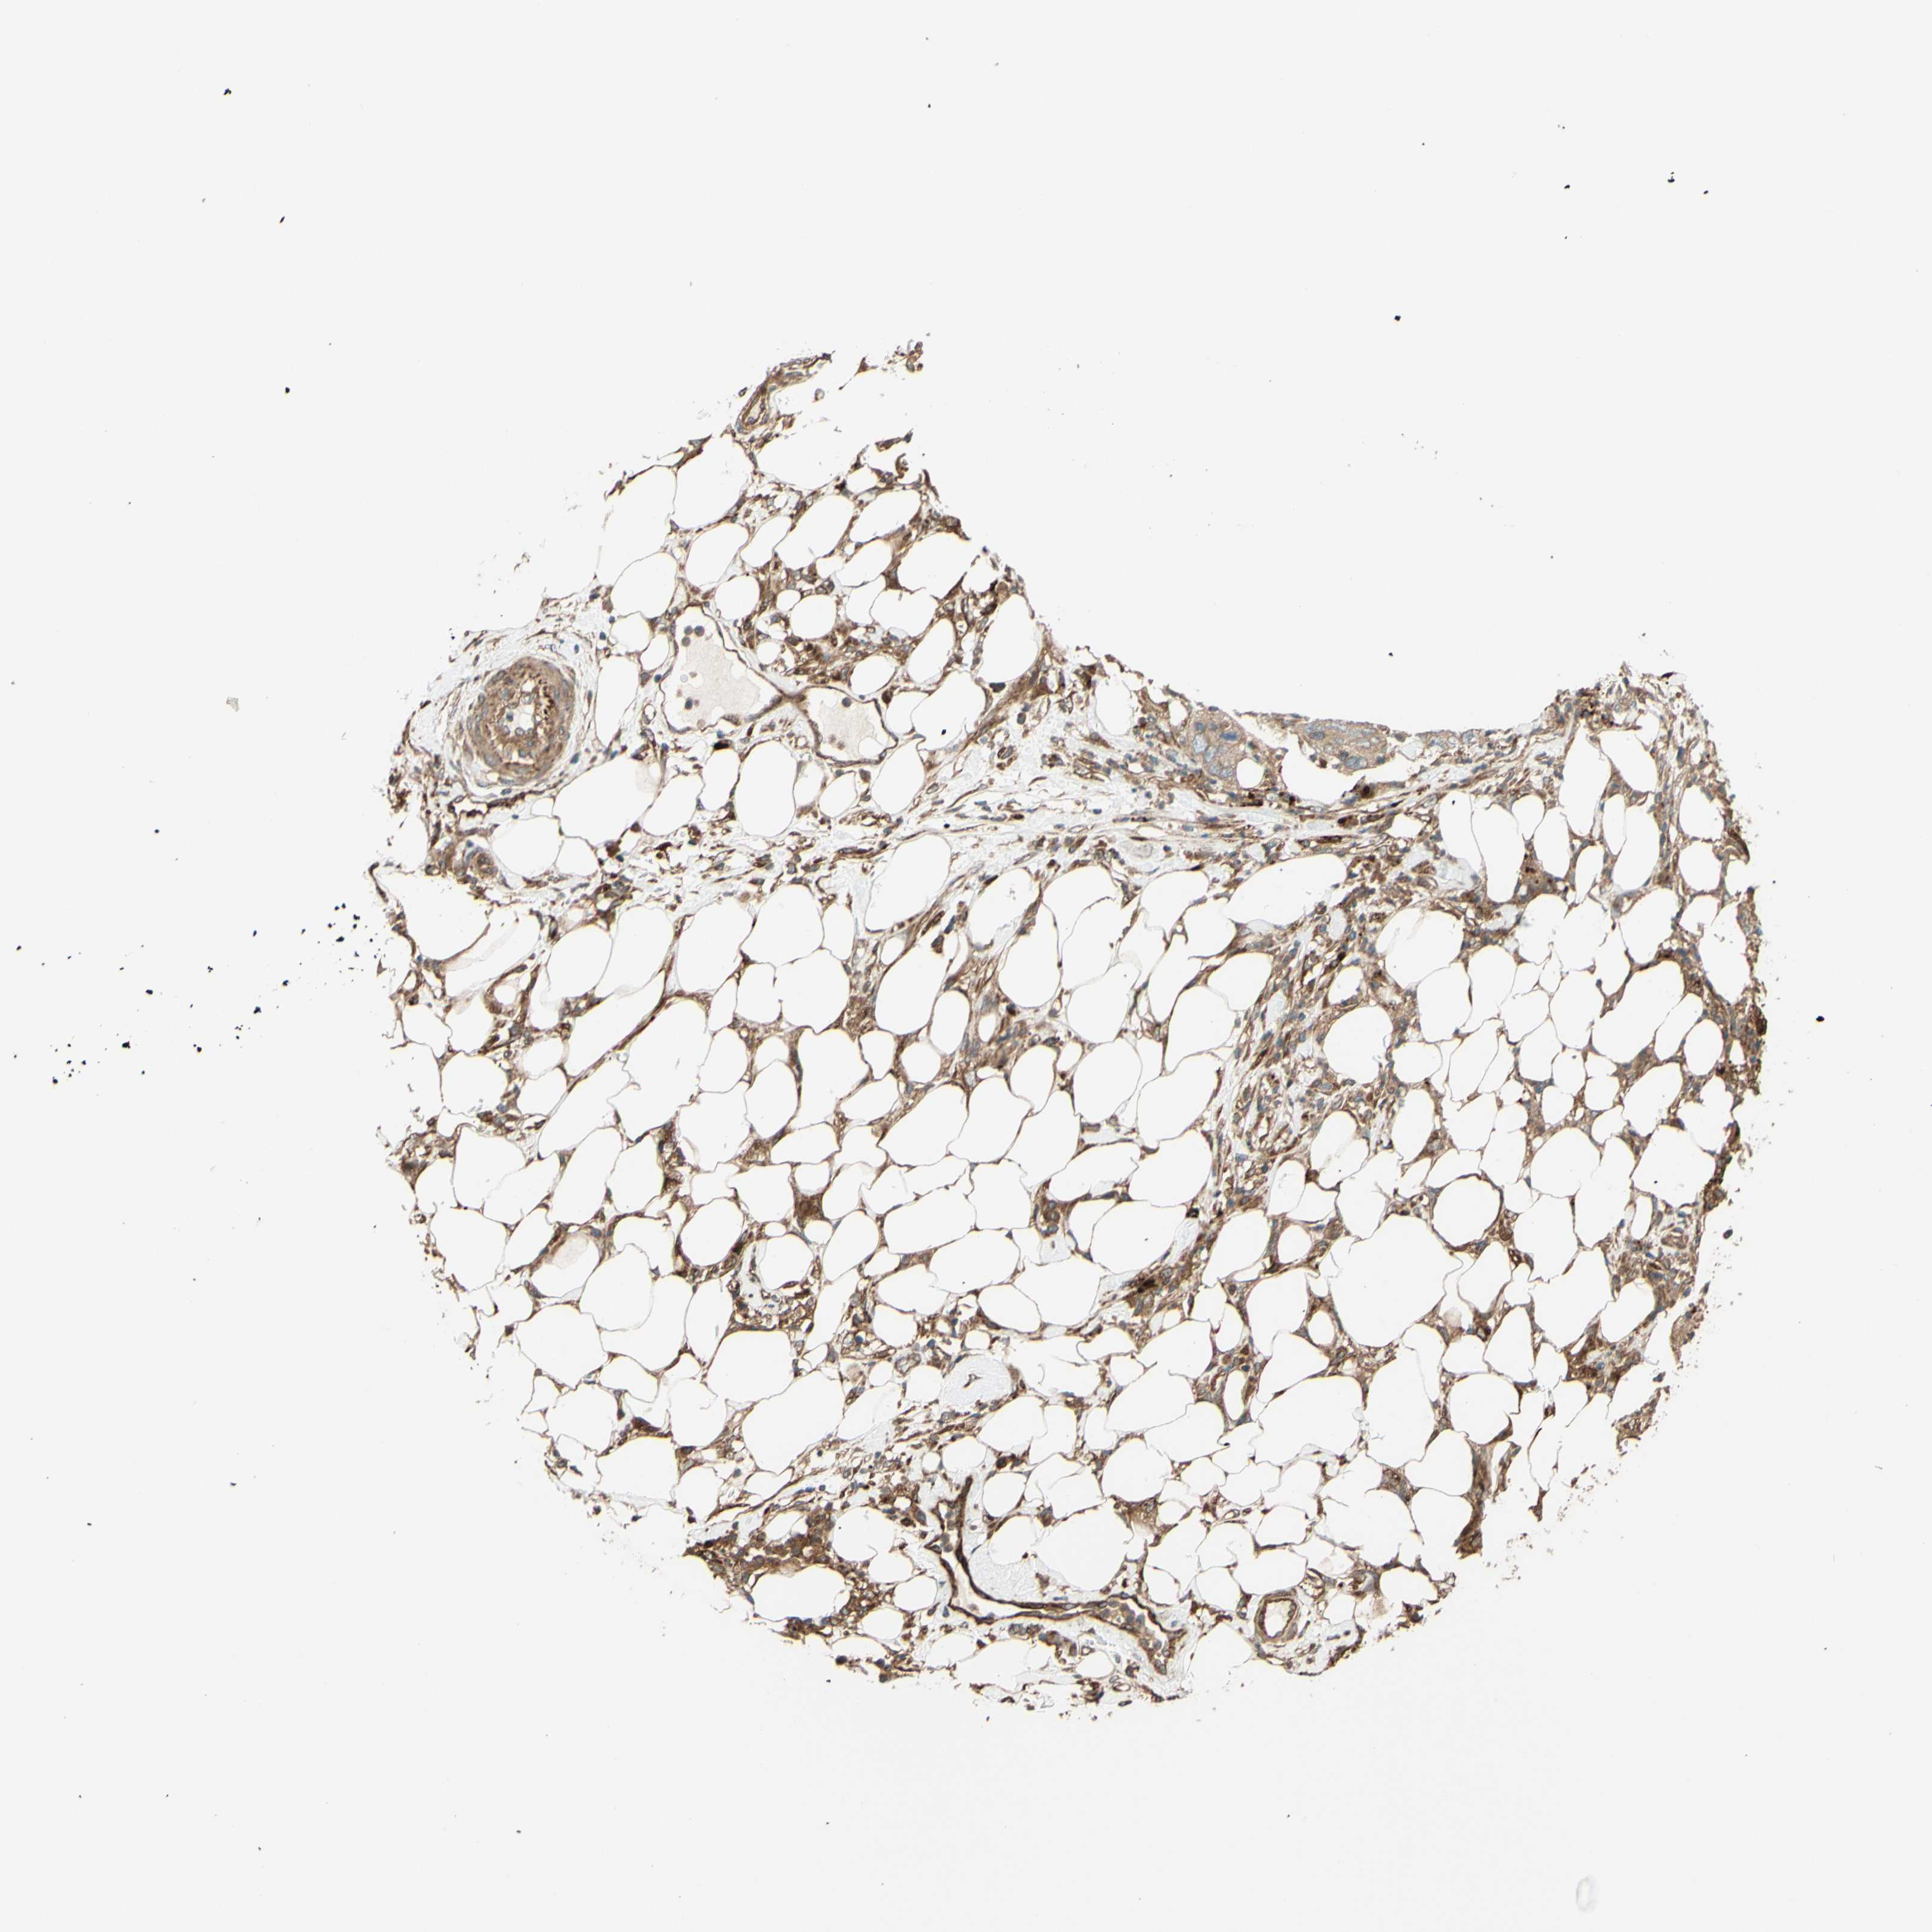

PANCREATIC CANCER - Protein expressioni

A mouse-over function shows sample information and annotation data. Click on an image to view it in a full screen mode. Samples can be filtered based on level of antibody staining by selecting one or several of the following categories: high, medium, low and not detected. The assay and annotation is described here.

Note that samples used for immunohistochemistry by the Human Protein Atlas do not correspond to samples in the TCGA dataset.

Antibody stainingi

Antibody staining in the annotated cell types in the current human tissue is reported as not detected, low, medium, or high, based on conventional immunohistochemistry profiling in selected tissues. This score is based on the combination of the staining intensity and fraction of stained cells.

Each image is clickable and will lead to virtual microscopy that enables deeper exploration of all samples and also displays staining intensity scores, fraction scores and subcellular localization as well as patient and tissue information for each sample.

Antibody HPA023652

Antibody CAB011455

Staining

High

Medium

Low

Not detected

Intensity

Strong

Moderate

Weak

Negative

Quantity

>75%

75%-25%

<25%

None

Location

Nuclear

Cytoplasmic/membranous

Cytoplasmic/membranous,nuclear

Adenocarcinoma, NOS

Adenocarcinoma, metastatic, NOS